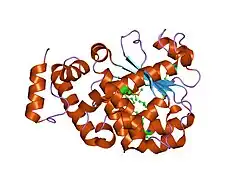

Alpha-tocopherol transfer protein (α-TTP) is a protein that in humans is encoded by the TTPA gene.[5][6][7]

- Meier R, Tomizaki T, Schulze-Briese C, et al. (2003). "The molecular basis of vitamin E retention: structure of human alpha-tocopherol transfer protein". J. Mol. Biol. 331 (3): 725–34. doi:10.1016/S0022-2836(03)00724-1. PMID 12899840.

- Min KC, Kovall RA, Hendrickson WA (2004). "Crystal structure of human alpha-tocopherol transfer protein bound to its ligand: implications for ataxia with vitamin E deficiency". Proc. Natl. Acad. Sci. U.S.A. 100 (25): 14713–8. doi:10.1073/pnas.2136684100. PMC 299775. PMID 14657365.

1oip: THE MOLECULAR BASIS OF VITAMIN E RETENTION: STRUCTURE OF HUMAN ALPHA-TOCOPHEROL TRANSFER PROTEIN

1oiz: THE MOLECULAR BASIS OF VITAMIN E RETENTION: STRUCTURE OF HUMAN ALPHA-TOCOPHEROL TRANSFER PROTEIN

1r5l: Crystal Structure of Human Alpha-Tocopherol Transfer Protein Bound to its Ligand